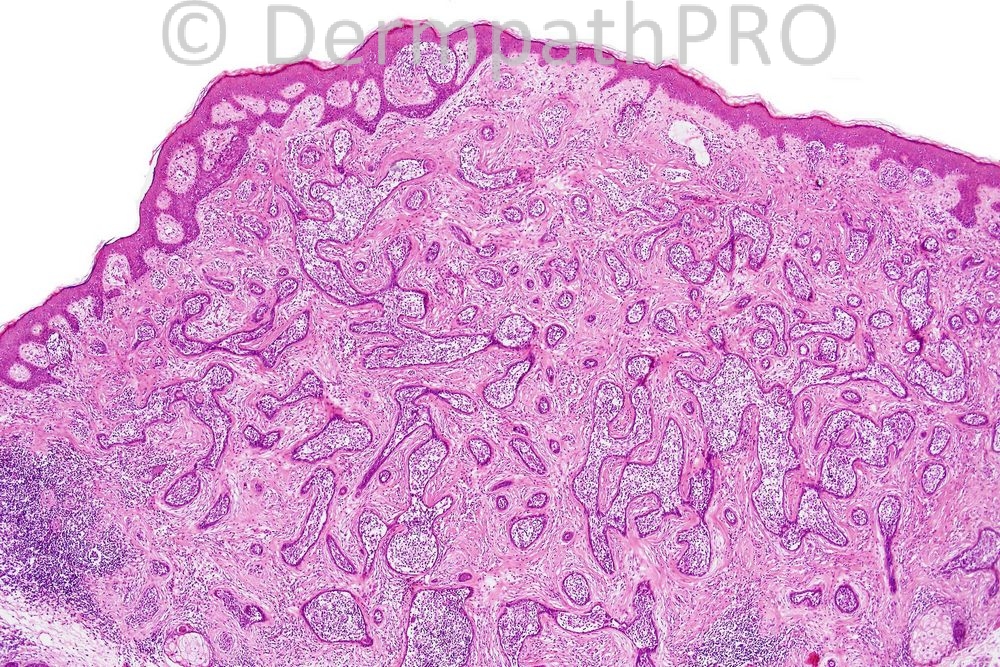

Female 36 years, nodule on forehead.

The diagnosis is Lymphadenoma cutis. Pablo Ortega it is great news you have such a case and as stated by Richard they are rare. well done all for making the correct diagnosis!